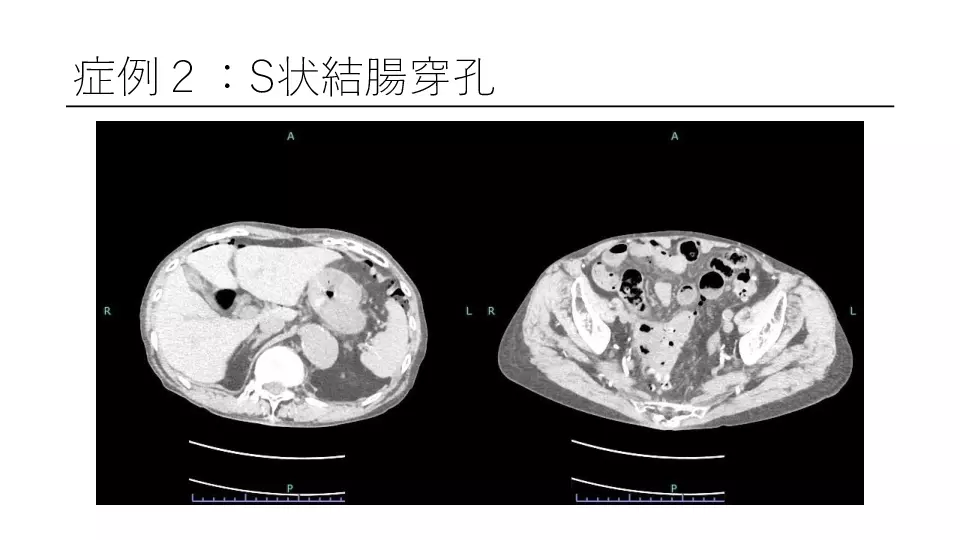

「反跳痛があります」と記載された紹介患者や、研修医からコンサルトにおいて、意外と腹膜炎ではないパターンが散見されます。 若手外科医だからこそ語れる腹膜炎のはなしを聞いてください。 #腹膜炎,#反跳痛の診かた,#コンサルト,

外科医目線の腹膜炎 ~これが腹膜刺激兆候です~